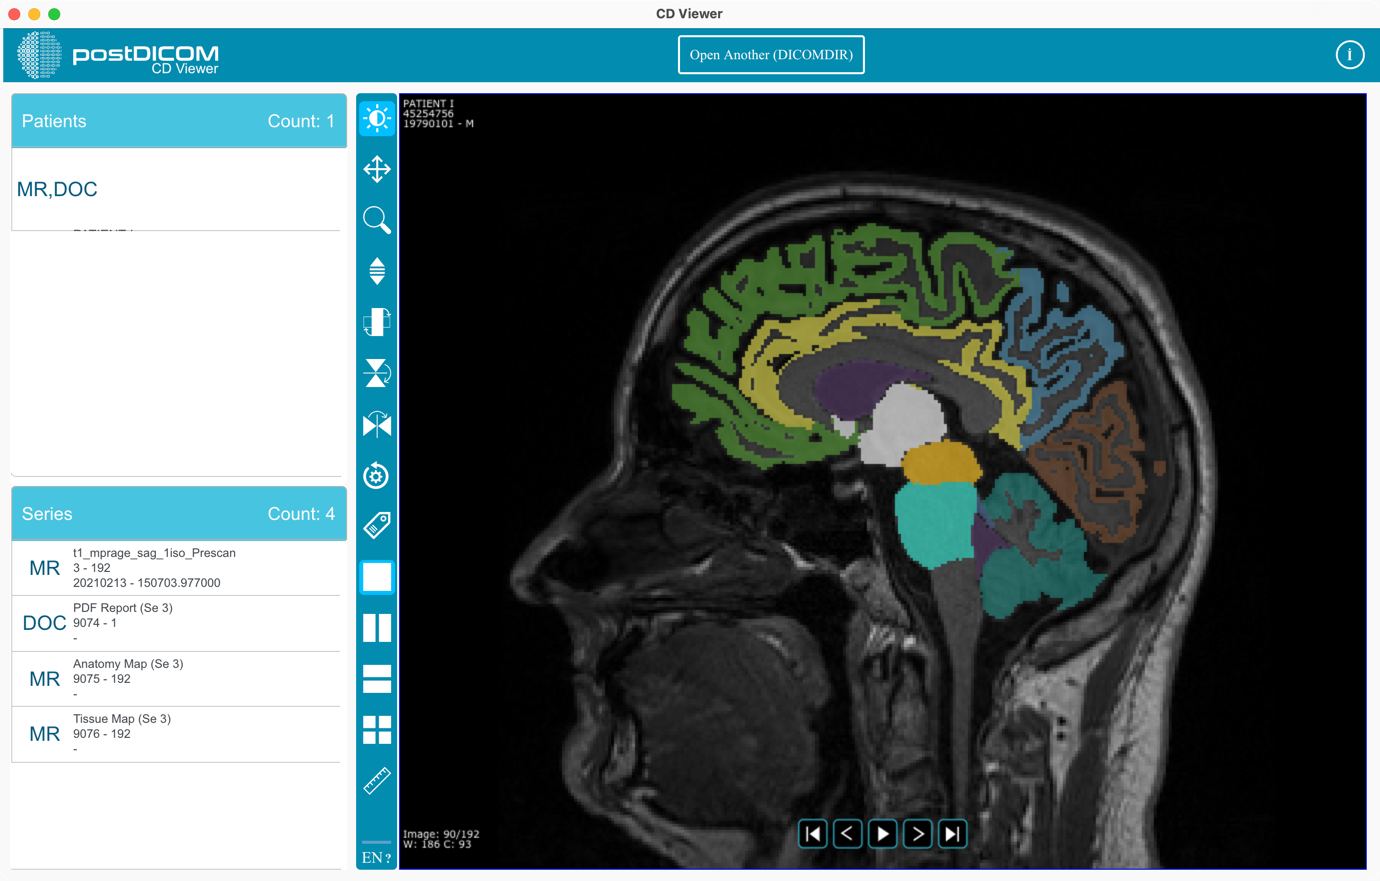

You can start using the application.